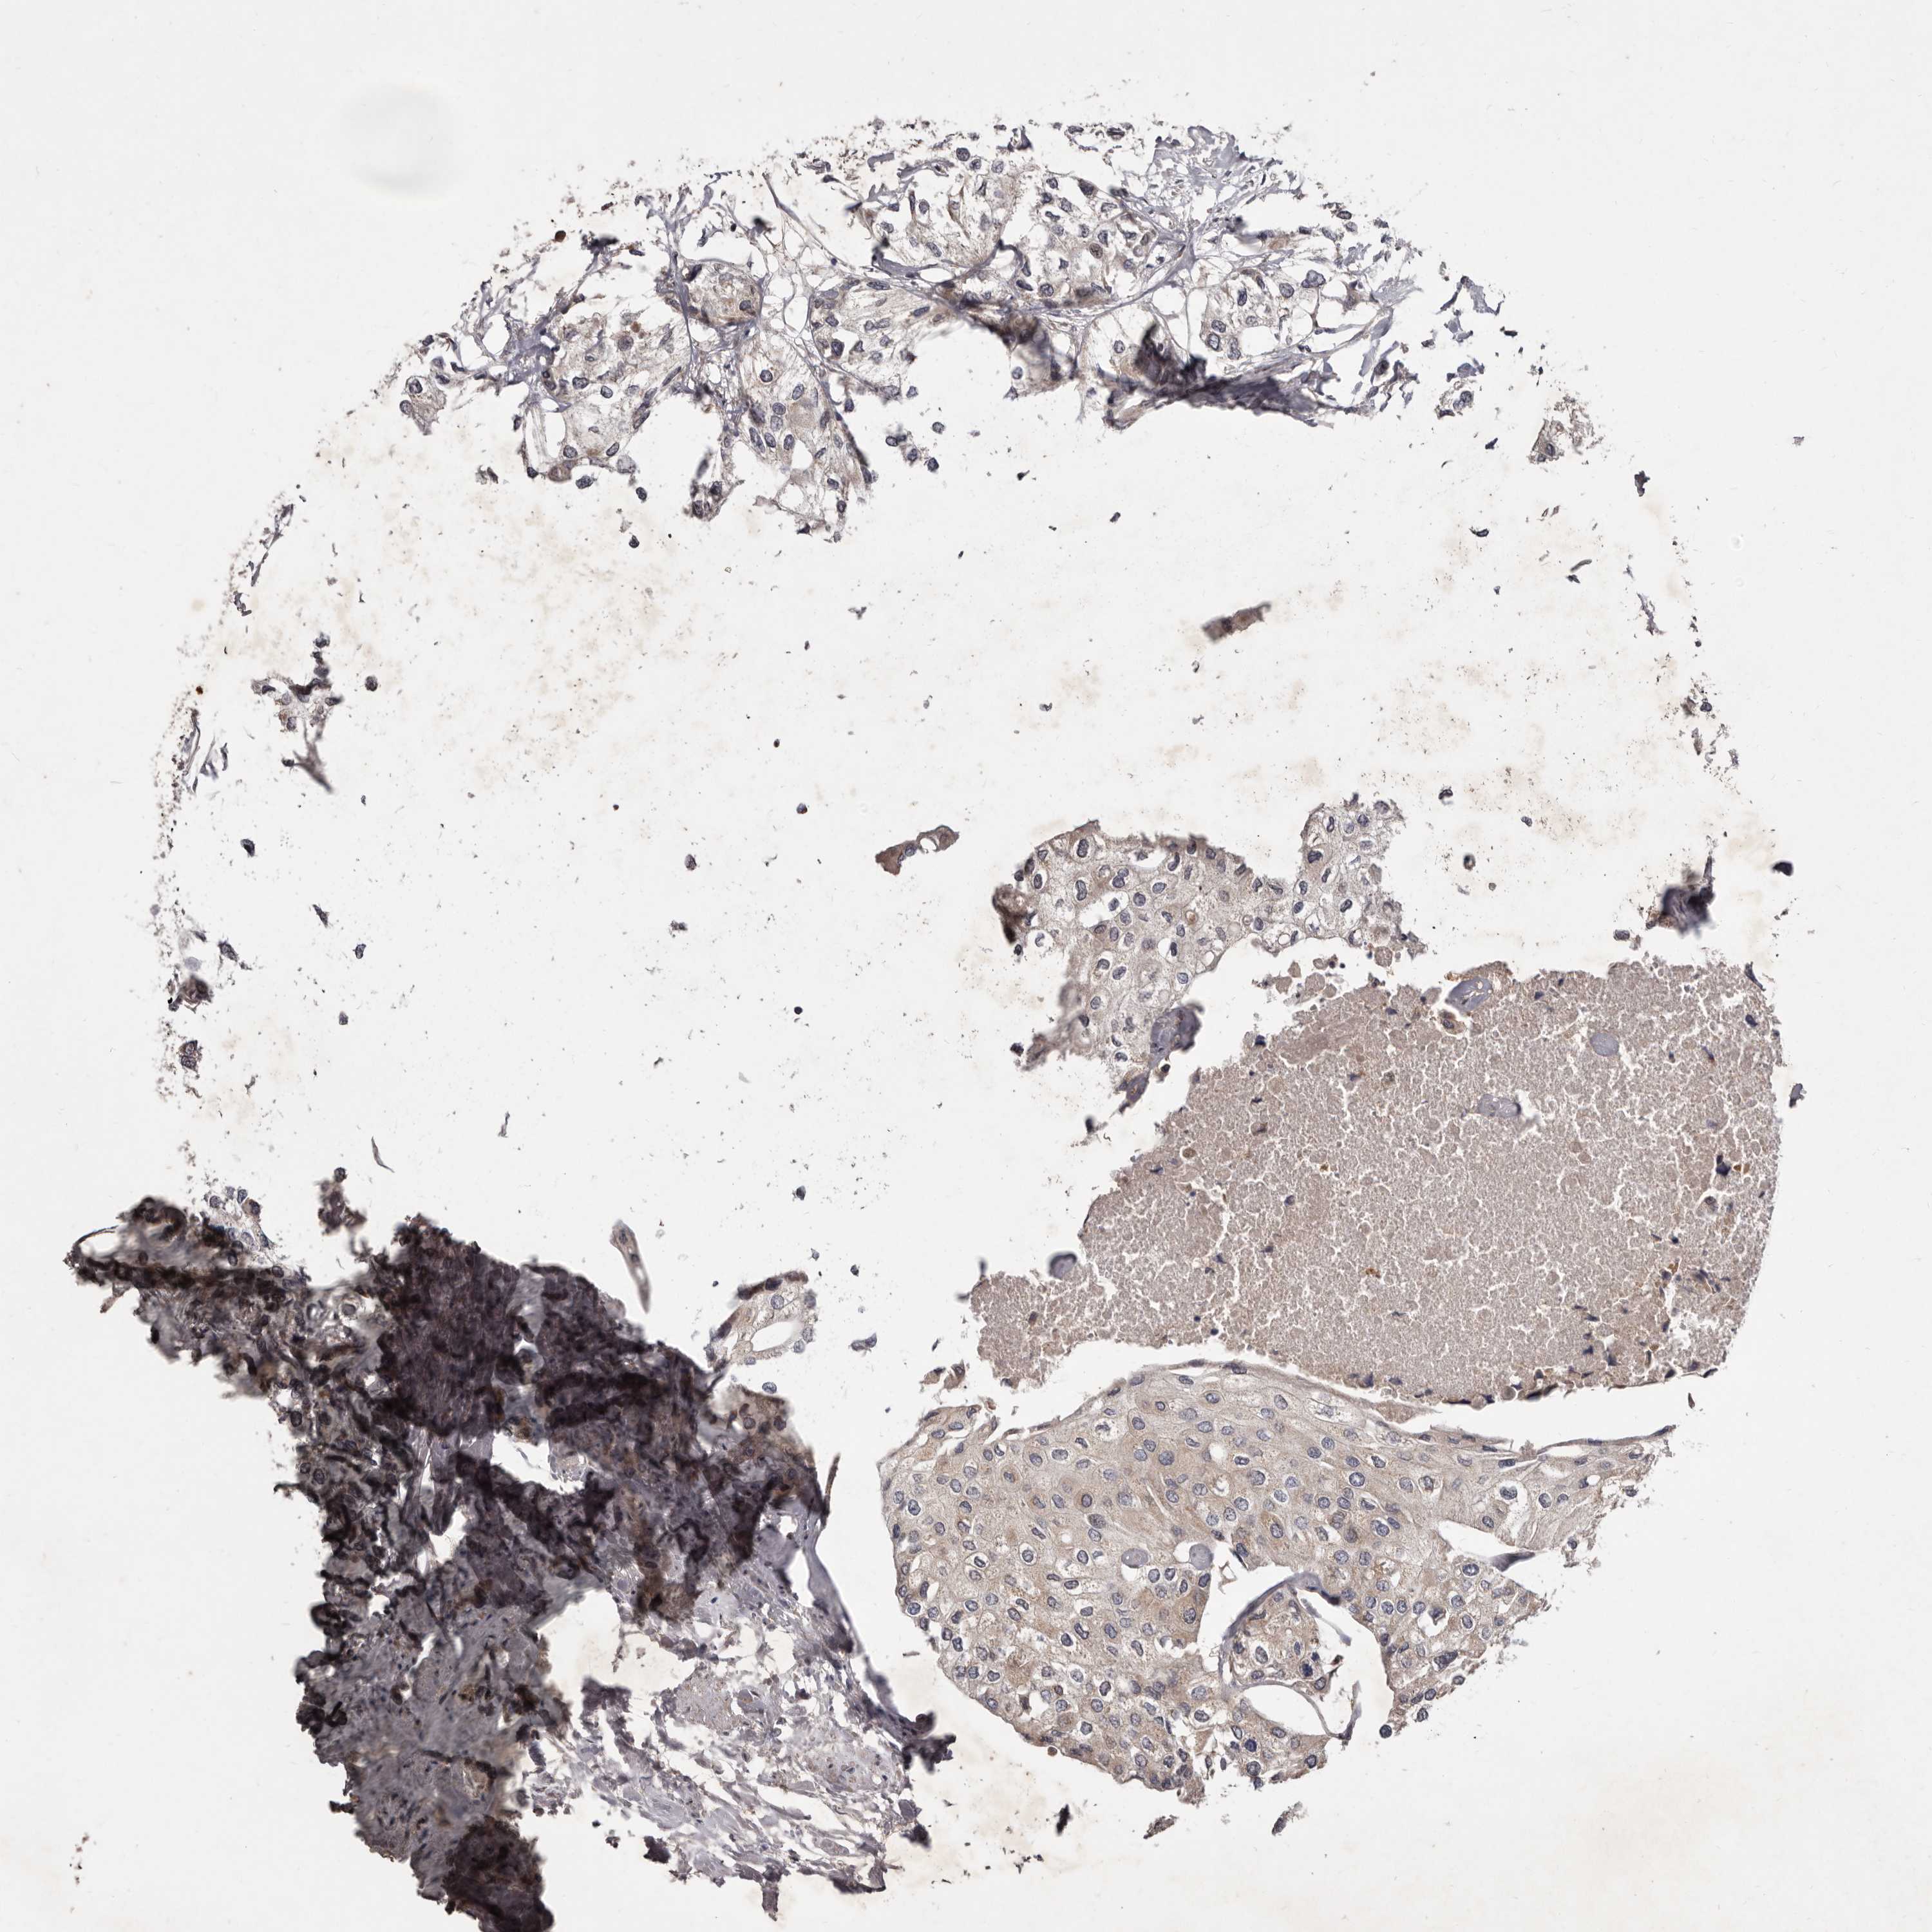

UROTHELIAL CANCER - Protein expressioni

A mouse-over function shows sample information and annotation data. Click on an image to view it in a full screen mode. Samples can be filtered based on level of antibody staining by selecting one or several of the following categories: high, medium, low and not detected. The assay and annotation is described here.

Note that samples used for immunohistochemistry by the Human Protein Atlas do not correspond to samples in the TCGA dataset.

Antibody stainingi

Antibody staining in the annotated cell types in the current human tissue is reported as not detected, low, medium, or high, based on conventional immunohistochemistry profiling in selected tissues. This score is based on the combination of the staining intensity and fraction of stained cells.

Each image is clickable and will lead to virtual microscopy that enables deeper exploration of all samples and also displays staining intensity scores, fraction scores and subcellular localization as well as patient and tissue information for each sample.

Antibody HPA028476

Antibody HPA028486

Antibody HPA028563

Staining

High

Medium

Low

Not detected

Intensity

Strong

Moderate

Weak

Negative

Quantity

>75%

75%-25%

<25%

None

Location

Nuclear

Cytoplasmic/membranous

Cytoplasmic/membranous,nuclear

Urothelial carcinoma, Low grade

Urothelial carcinoma, High grade